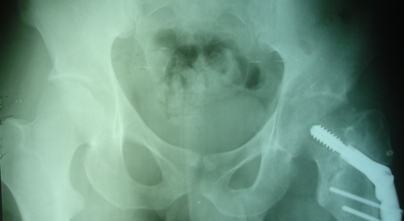

Уважаемые коллеги, приношу извинения за перерыв в работе -

был в командировке. За это время больному сделали КТ и,  сегодня,

снимки. Укорочение конечности - 1-1,5 см, ШДУ-115 градусов, замедленная консолидация,

остеопороз.

Вопрос о тактике дальнейшего ведения пациента (напоминаю, возраст 19

лет)?